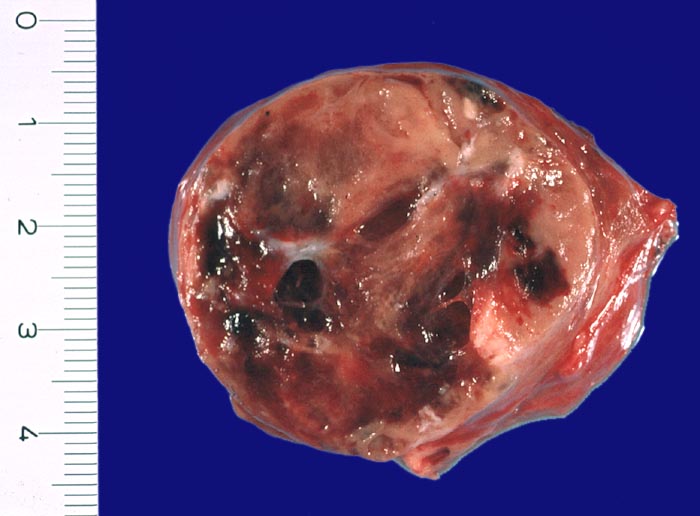

• Anschnitt eines grossen mikrofollikulären Knotens (autonomes Adenom) mit angedeuteter Kapsel und zentraler Einblutung. Oben zwei weitere kleine Satellitenknoten.

Makroskopie